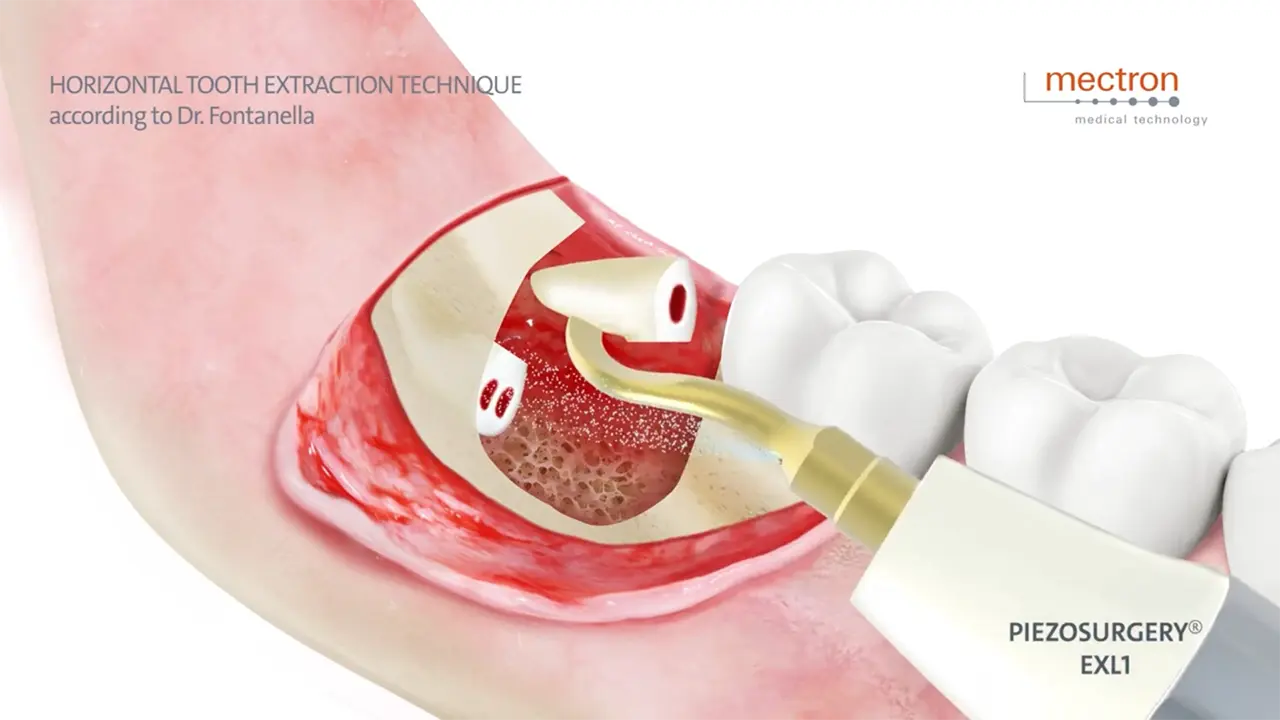

PIEZOSURGERY® Extractions

Dr. Fabrizio Fontanella

Horizontal tooth extraction technique